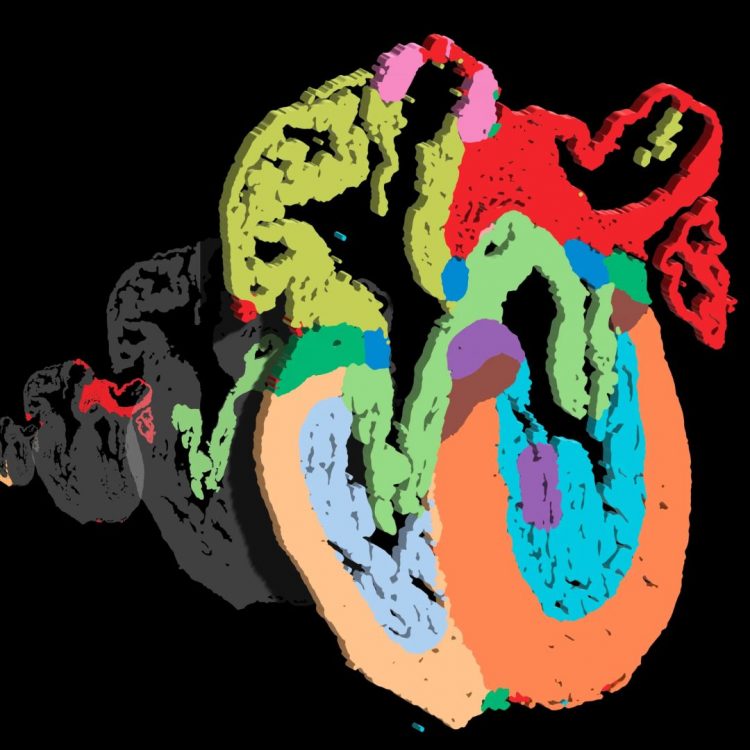

Un grupo de científicos ha conseguido crear un mapa tridimensional del corazón humano en formación con una resolución unicelular.

El mapa reveló la distribución específica de diversas subpoblaciones de células cardíacas, evidenciando cómo estas células interactúan entre sí durante el proceso de desarrollo del corazón.

El análisis a nivel celular identificó un total de 75 subpoblaciones que exhibían características acordes con su ubicación anatómica y su etapa de desarrollo, lo que incluye la identificación de nuevos subtipos de células en las válvulas cardíacas.

Asimismo, los autores encontraron interacciones entre combinaciones particulares de poblaciones celulares. Por ejemplo, identificaron interacciones entre las células del músculo cardíaco ventricular, los fibroblastos (componentes del tejido conectivo) y las células endoteliales (que recubren los vasos sanguíneos), las cuales podrían desempeñar un papel en la formación de la pared ventricular.